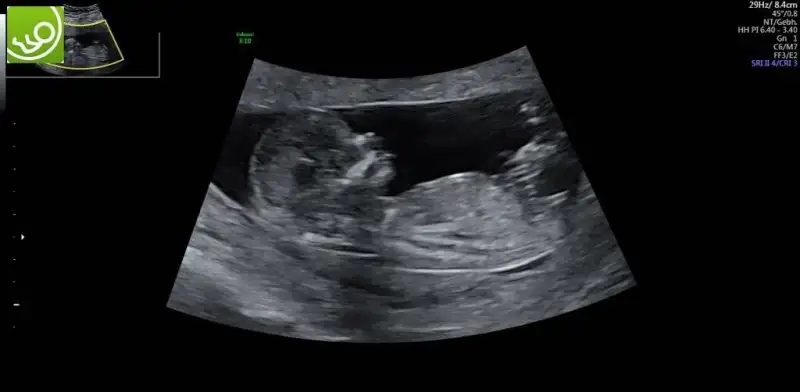

Merhaba kızlar 13 haftalık gebeyim ateşim iki gündür 38. Düşmüyor. Çok korkuyorum aranızda böyle bir sıkıntı yaşayan var mı

kizlar iki gunden beri icimi kemiren bisi var sizlerle paylasmak istiyorum yardimci olursaniz sevinirim ikili test yaptirdik bildiginiz uzere dr hersey normal dedi ve kan testi icin hafta ya gun verdi test kagidinda birtek mide cebi gorulmemistir yaziyordu dr haftaya gelince tekrar bakariz dedi hersey normal dedu ama benim icim icimi yiyor ne olur dua edin ve yardimci olun boyle bisi duyan varsa bilgi paylasabilir mi

Bazı organlar 13.haftada daha rahat görünüyor canım, o yüzdendir. Bizde iki hafta sonra yine gideceğiz ki kalpteki 4 odacığı görmek için. Rahat olmaya çalışalım olur mu?

Bazen bebegin pozisyonundan dolayi tam istedikleri gibi net goremeyebiliyorlar. Onun icin tekrar bakilacak demis olabilir.Net gormeden rapora yazmak istememis olabilir.